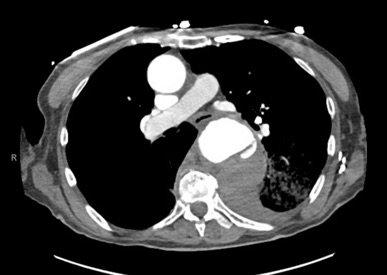

The patient’schest X-ray revealed a prominent mediastinum and opacification in the left middle and lower lung fields. The CT showed an aortic aneurysm extending from the thorax to the abdomen with rupture near T7 (blue arrow). It also showed periaortic hemorrhage with active extravasation (green arrow) likely secondary to a penetrating ulcer and bilateral pulmonary opacities concerning for hemothorax (pink arrow).